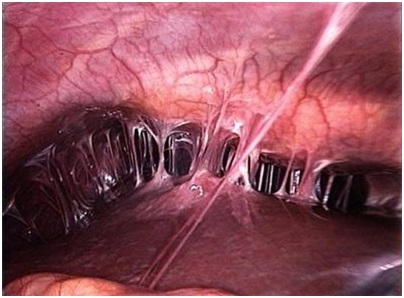

Лапароскопия – это хирургическое лечение относящееся к малоинвазивным вмешательствам. Этот метод заключается в осуществлении врачом нескольких небольших разрезов, через которые вводятся инструменты и манипулятор. В ходе операции производится рассечение спаек и прижигание сосудов. Также врач должен удалить синехии. Это производится с помощью лазера, аквадиссекции или электрохирургии.